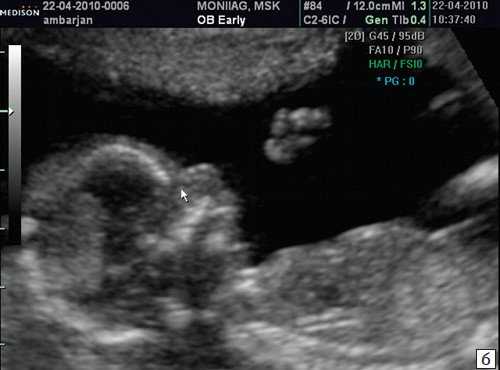

Если все критерии соблюдены, то на уровне носа плода должны быть видны три четко различимые линии: верхняя линия представляет собой кожу, книзу от нее визуализируется более толстая и более эхогенная, чем кожа носовая кость. Третья линия, визуализируемая кпереди от носовой кости и на более высоком уровне, чем кожа - это кончик носа (рис. 1).

Рис. 1. Нормальная носовая кость.

Считается, что носовая кость нормальна, когда она по своей структуре более эхогенна, чем надлежащая кожа и патологична, если она не видна (аплазия) (рис. 2) или ее длина меньше нормы (гипоплазия) (рис. 3). В случае одинаковой или меньшей эхогенности носовой кости чем кожи носовая кость считается патологической (рис. 4).

а) Стрелкой указана эхогенная кожа плода.

б) Стрелкой указано отсутствие носовой кости.